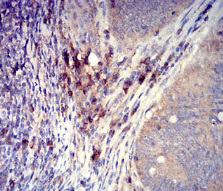

IHC    1/200 - 1/1000